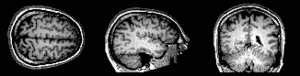

У більшості тварин, за винятком тих, у яких наявна дифузна нервова система, анатомічно виділяють центральну та периферичну частини, або центральну (ЦНС) та периферичну (ПНС) нервові системи. Якщо взяти хребетних, то у них центральна нервова система, складається з головного мозку та спинного мозку.[29] Головний мозок у свою чергу ділиться на ряд менших частин, які мають специфічну будову та забезпечують специфічні функції: довгастий мозочок, міст (тільки у ссавців і, можливо, у птахів), мозочок, середній мозок, проміжний мозок та кінцевий мозок.[32] Від головного мозку відходять черепні нерви, а від спинного – спинномозкові нерви. Ці дві групи нервів разом з нервовими вузлами та нервовими сплетеннями утворюють периферичну нервову систему.[29][33]